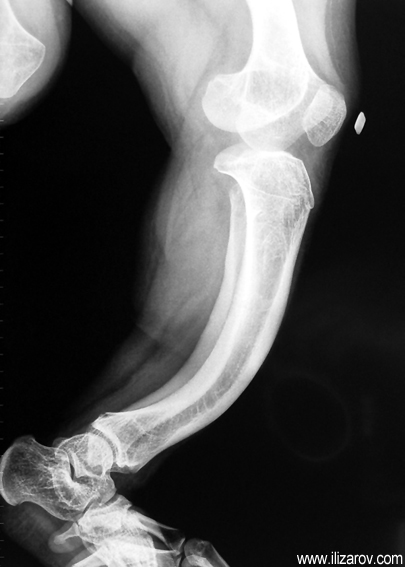

In hypophosohatemic rickets, abnormal bone findings become evident after 1 year of age; there are short stature and deformities around the knee (bilateral genu valgum or varum, tibial torsion, deformity at tibia and femur, ‘windswept’ deformity).

Because the deformity caused by hypophosphatemic rickets is very close to the growth plate, a significant deformity and malalignment occurs. For that reason, more than one deformity centers (CORA) are found at preoperative evaluation, and osteotomy at more than one level is required to correct the deformity. The most frequently used methods to correct the deformity are acute or gradual deformity correction using the Ilizarov method or unilateral external fixator. In the ‘fixator assisted nailing’ technique, which is applied in our department, the deformity is corrected in an acute fashion with the help of an external fixator, and the extremity is stabilized by an intramedullaru nail. The external fixator is removed before the end of the surgery if no gradual lengthening is planned postoperatively. If lengthening (over nail) is planned, the fixator is removed after the completion of the lengthening procedure. As a result, the risk of pin tract infection is eliminated, correction loss and relapsing of the deformity (which are important problems in the treatment of hypophosphatemic rickets) are avoided, eary motion and full weight bearing are allowed, and comfortability of the patient is improved because the duration with external fixator is decreased.